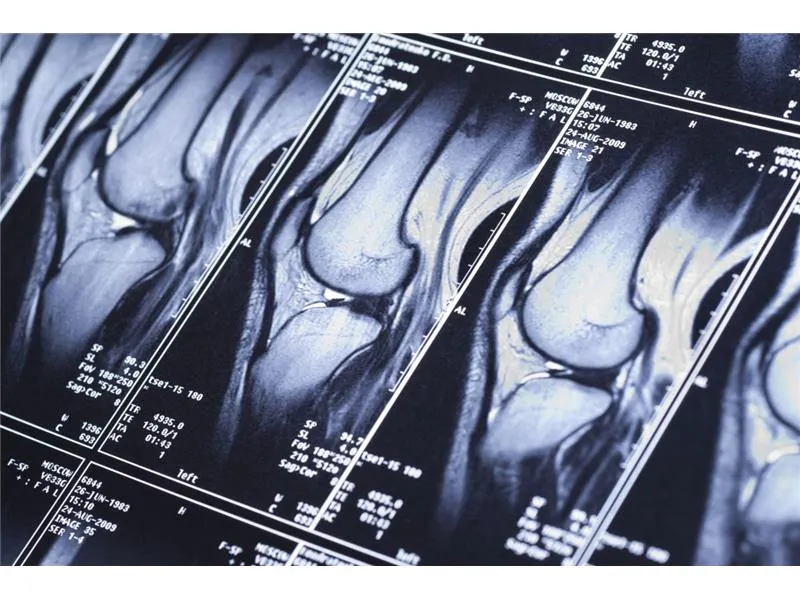

- Ortopeda – zajmuje się problemami z układem mięśniowo-szkieletowym, może zlecić MRI w przypadku urazów stawów lub podejrzeń o zmiany degeneracyjne.

Wraz z postępem technologicznym, diagnostyka rezonansu magnetycznego staje się coraz bardziej zaawansowana, co wpływa na sposób, w jaki lekarze podejmują decyzje dotyczące skierowań i leczenia. Nowe techniki, takie jak rezonans magnetyczny o wysokiej rozdzielczości czy funkcjonalny rezonans magnetyczny (fMRI), umożliwiają bardziej precyzyjne obrazowanie struktur wewnętrznych ciała oraz ocenę funkcji mózgu. Dzięki tym innowacjom specjaliści mogą lepiej analizować wyniki badań, co prowadzi do szybszego i dokładniejszego postawienia diagnozy.